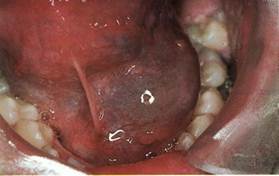

Киста подъязычной слюнной железы располагается в переднебоковом отделе дна полости рта вблизи уздечки языка.

Клиника. Определя­ется в виде выбухания овальной формы, покрытого неизмененной слизистой оболочкой. При истончении слизистой оболочки стенка кисты просвечивается и имеет голубоватый оттенок. Киста связана с одним из участков железой или со всей подъязычной слюнной железой. Растет медленно, месяцами, не причиняет боли и только, когда приобретает значительные размеры, обращает на себя внимание вследствие нарушения речи, затруднения во время приема пищи. Большая киста может смещать язык кзади и распространяться за среднюю линию дна полости рта или в поднижнечелюстную область. Пальпаторно киста пред­ставляет мягкое образование с флюктуацией, иногда консистенция более эластичная. При прорыве оболочки обильно выделяется тягучая прозрачная жидкость и киста не контурируется. По истечении време­ни киста наполняется и снова становится видимой.